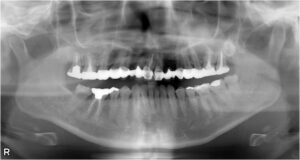

下顎臼歯2本欠損症例

BEFORE AFTER 68歳女性/下2本欠損/インプラント埋込手術 【治療内容】 左下に入っているブリッジからの出血…